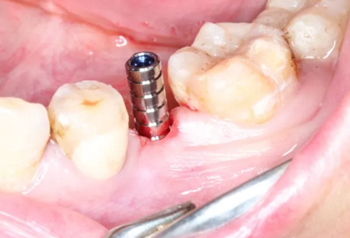

根據(jù)上述植入和修復(fù)方案,立體設(shè)計Implant Guide™全程導(dǎo)板,鑒于下頜需避讓下頜神經(jīng)管,并考慮到種植體與頰舌側(cè)、近遠中側(cè)的關(guān)系,設(shè)計在該牙位植入1顆Alpha-Bio Tec ICE 4.2x 10mm的植體。

3.根據(jù)手術(shù)計劃書,使用術(shù)前所設(shè)計好的長度、直徑的一系列鉆針在導(dǎo)板的引導(dǎo)下進行備孔。

4.在全程導(dǎo)板的引導(dǎo)下,使用全程導(dǎo)板工具盒中的攜帶器,從導(dǎo)板套環(huán)孔處將植體植入,直至攜帶器的六角、與導(dǎo)板套環(huán)的六角嚴絲合縫(如圖,六角對六角),即表示植體就位成功。